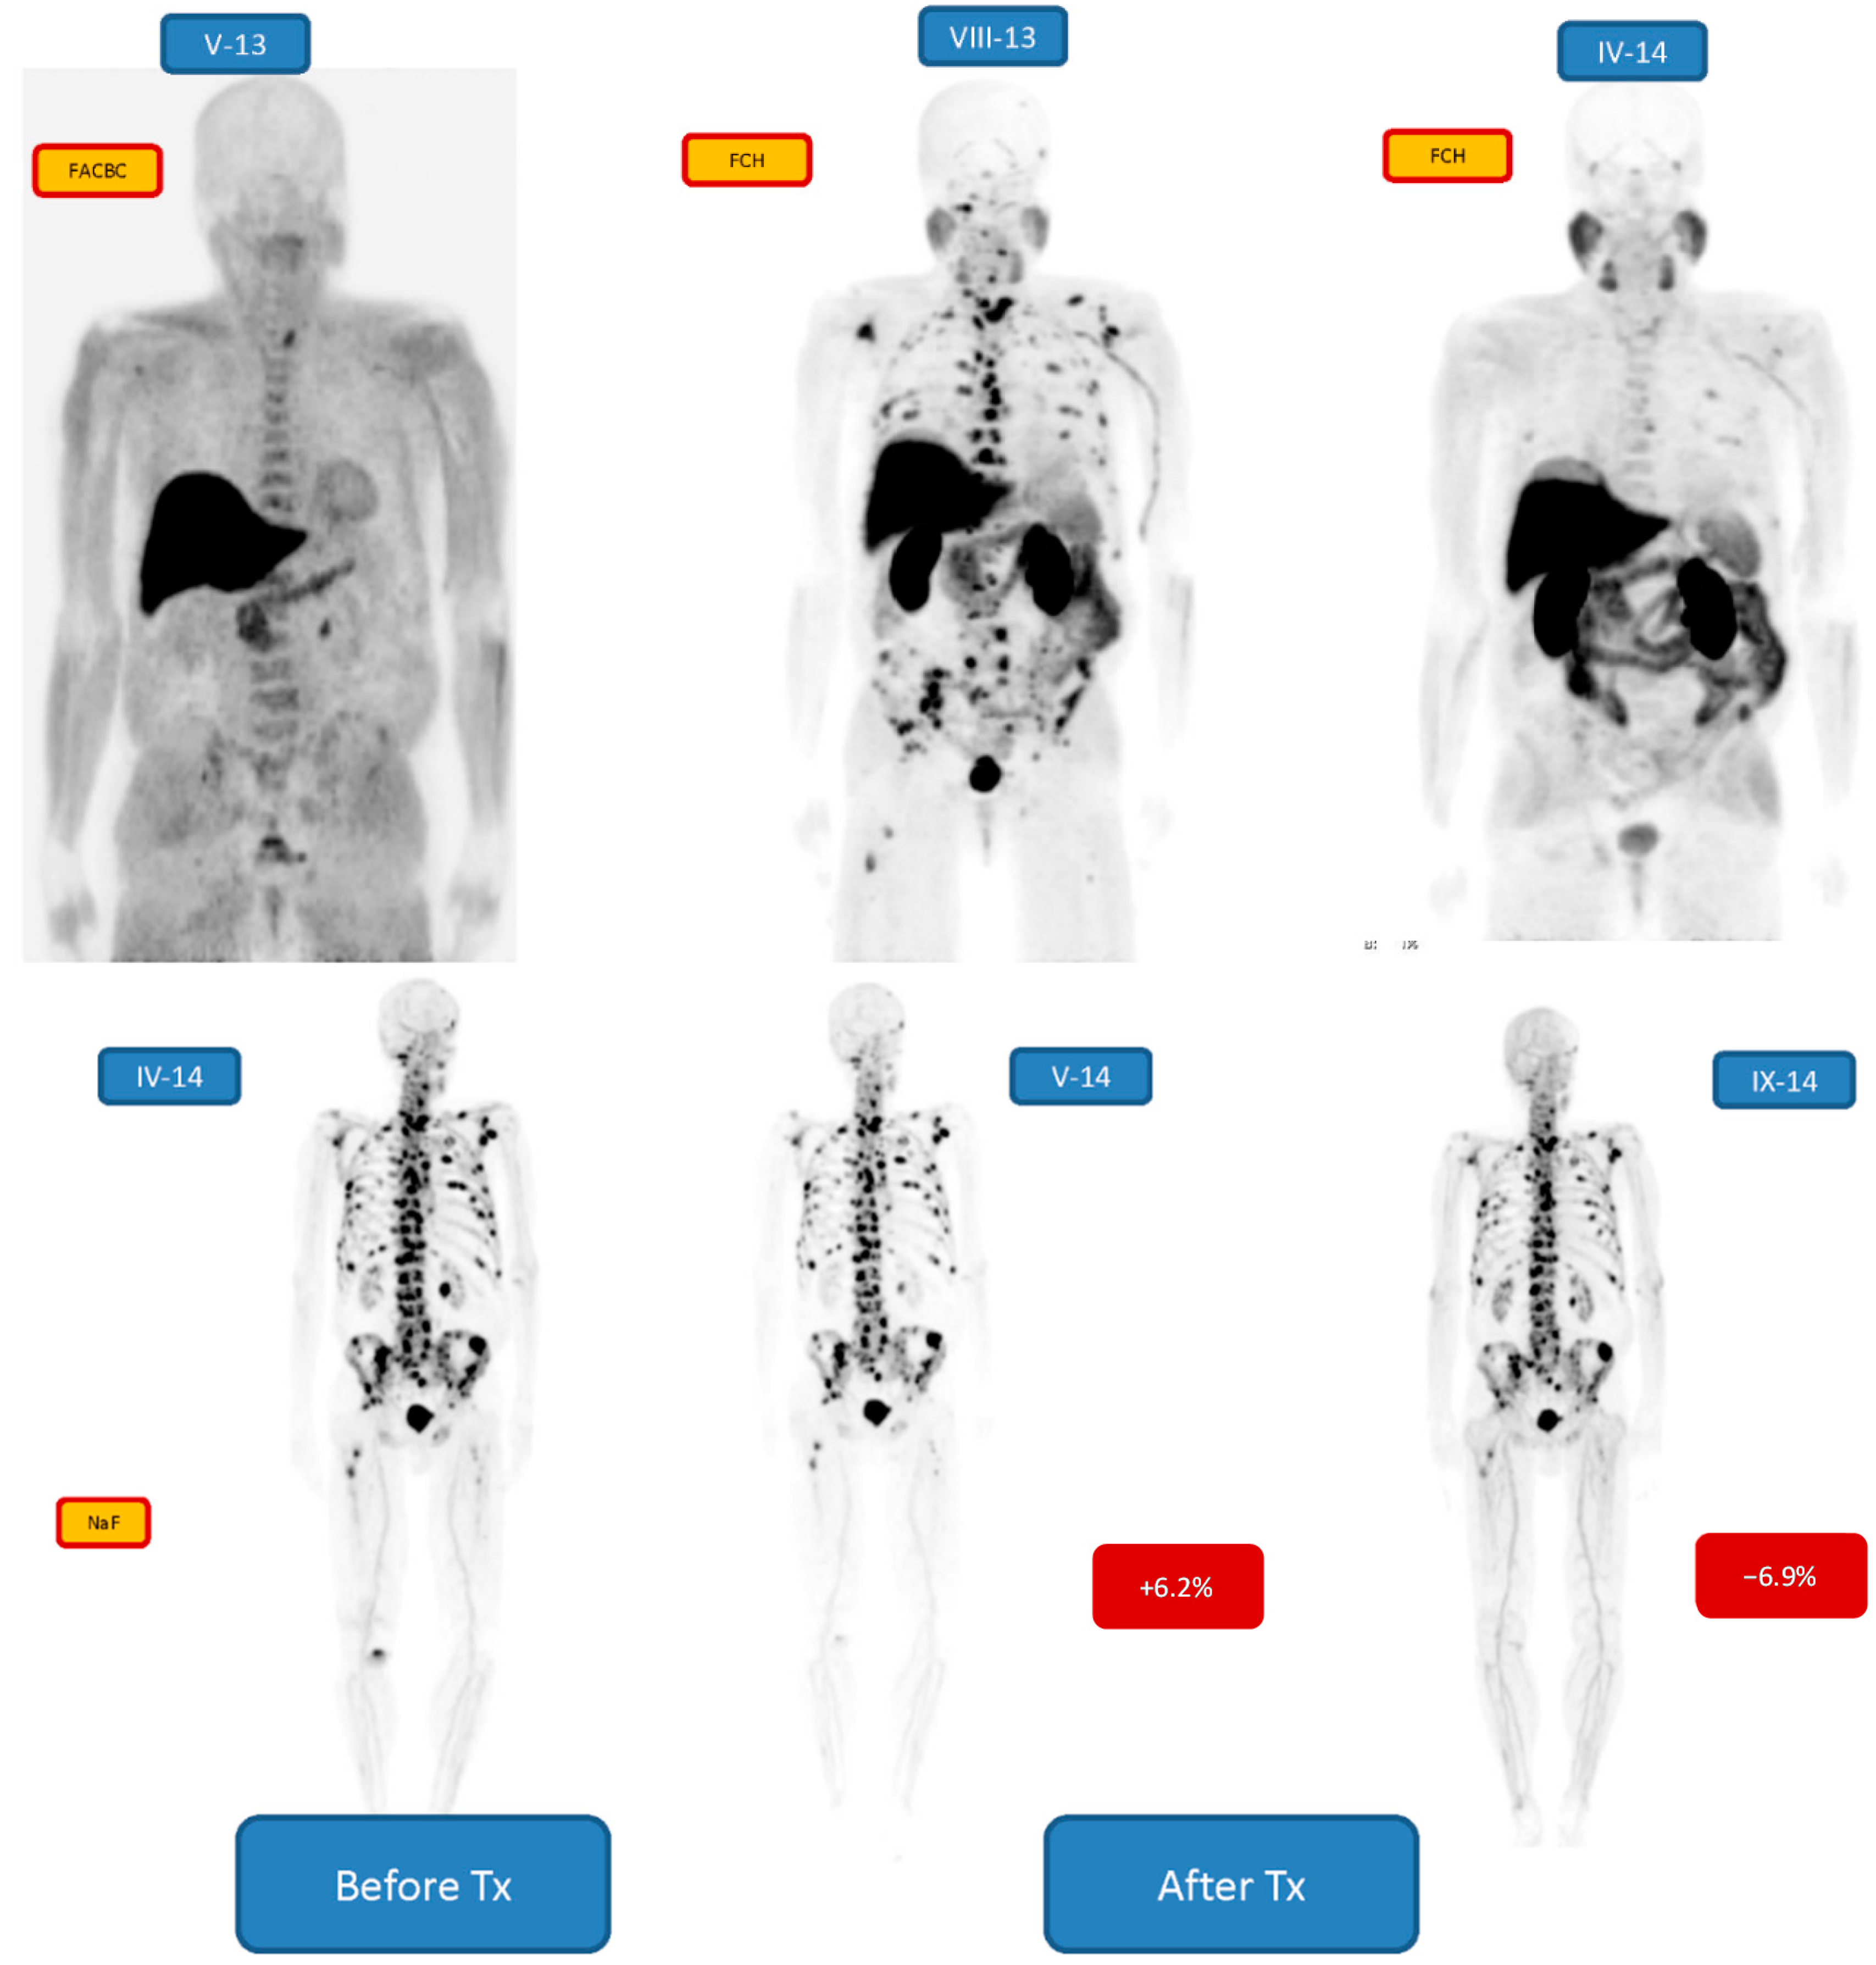

| 2 m/77 | GS 7, pT3N0M0 (-01) | Bone | NaF, FCH, FACBC, MRI, CT | 6 24.80 MBq | 5.5 | RRP, EBRT (PO), Bicalutamide, Docetaxel, Abiraterone, Enzalutamide, Denosumab, Goserelin |

| 2 m/77 | Bone 2/3 | +6.2/−6.9 | 6 24.80 MBq | PR | Enzalutamide, Denosumab, Goserelin |